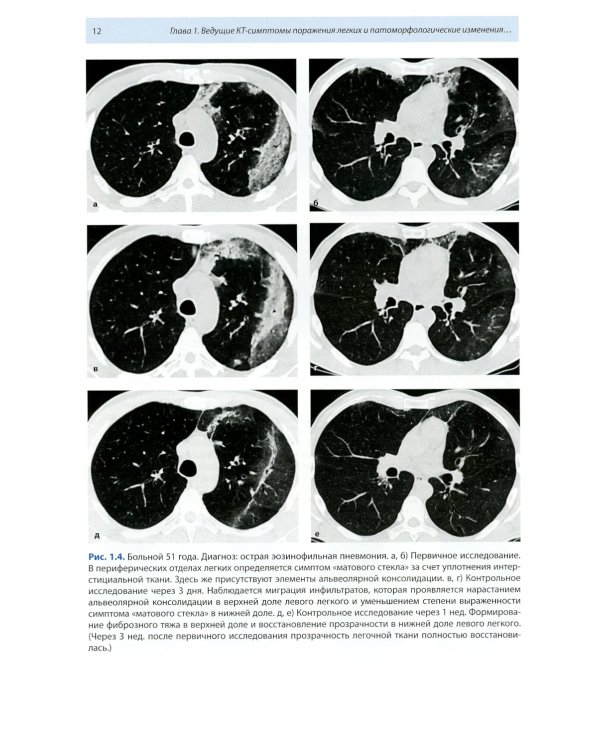

Книга составлена из двух разделов. В первом (глава 1) описаны основные симптомы патологии легких, выявляемые при КТ. Каждый из них представлен с позиции отображающих его морфологических изменений. В краткой форме описаны заболевания, проявляющиеся конкретным симптомом. Второй раздел книги состоит из трех глав, в которых отражены современные взгляды на наиболее часто встречающуюся патологию легких (пневмония, туберкулез, рак) и показаны возможности КТ в выявлении этих заболеваний. Издание предназначено для врачей лучевой диагностики, терапевтов, интернов и студентов старших курсов, интересующихся проблемами рентгенологии.| Издательство | МЕДпресс-информ |